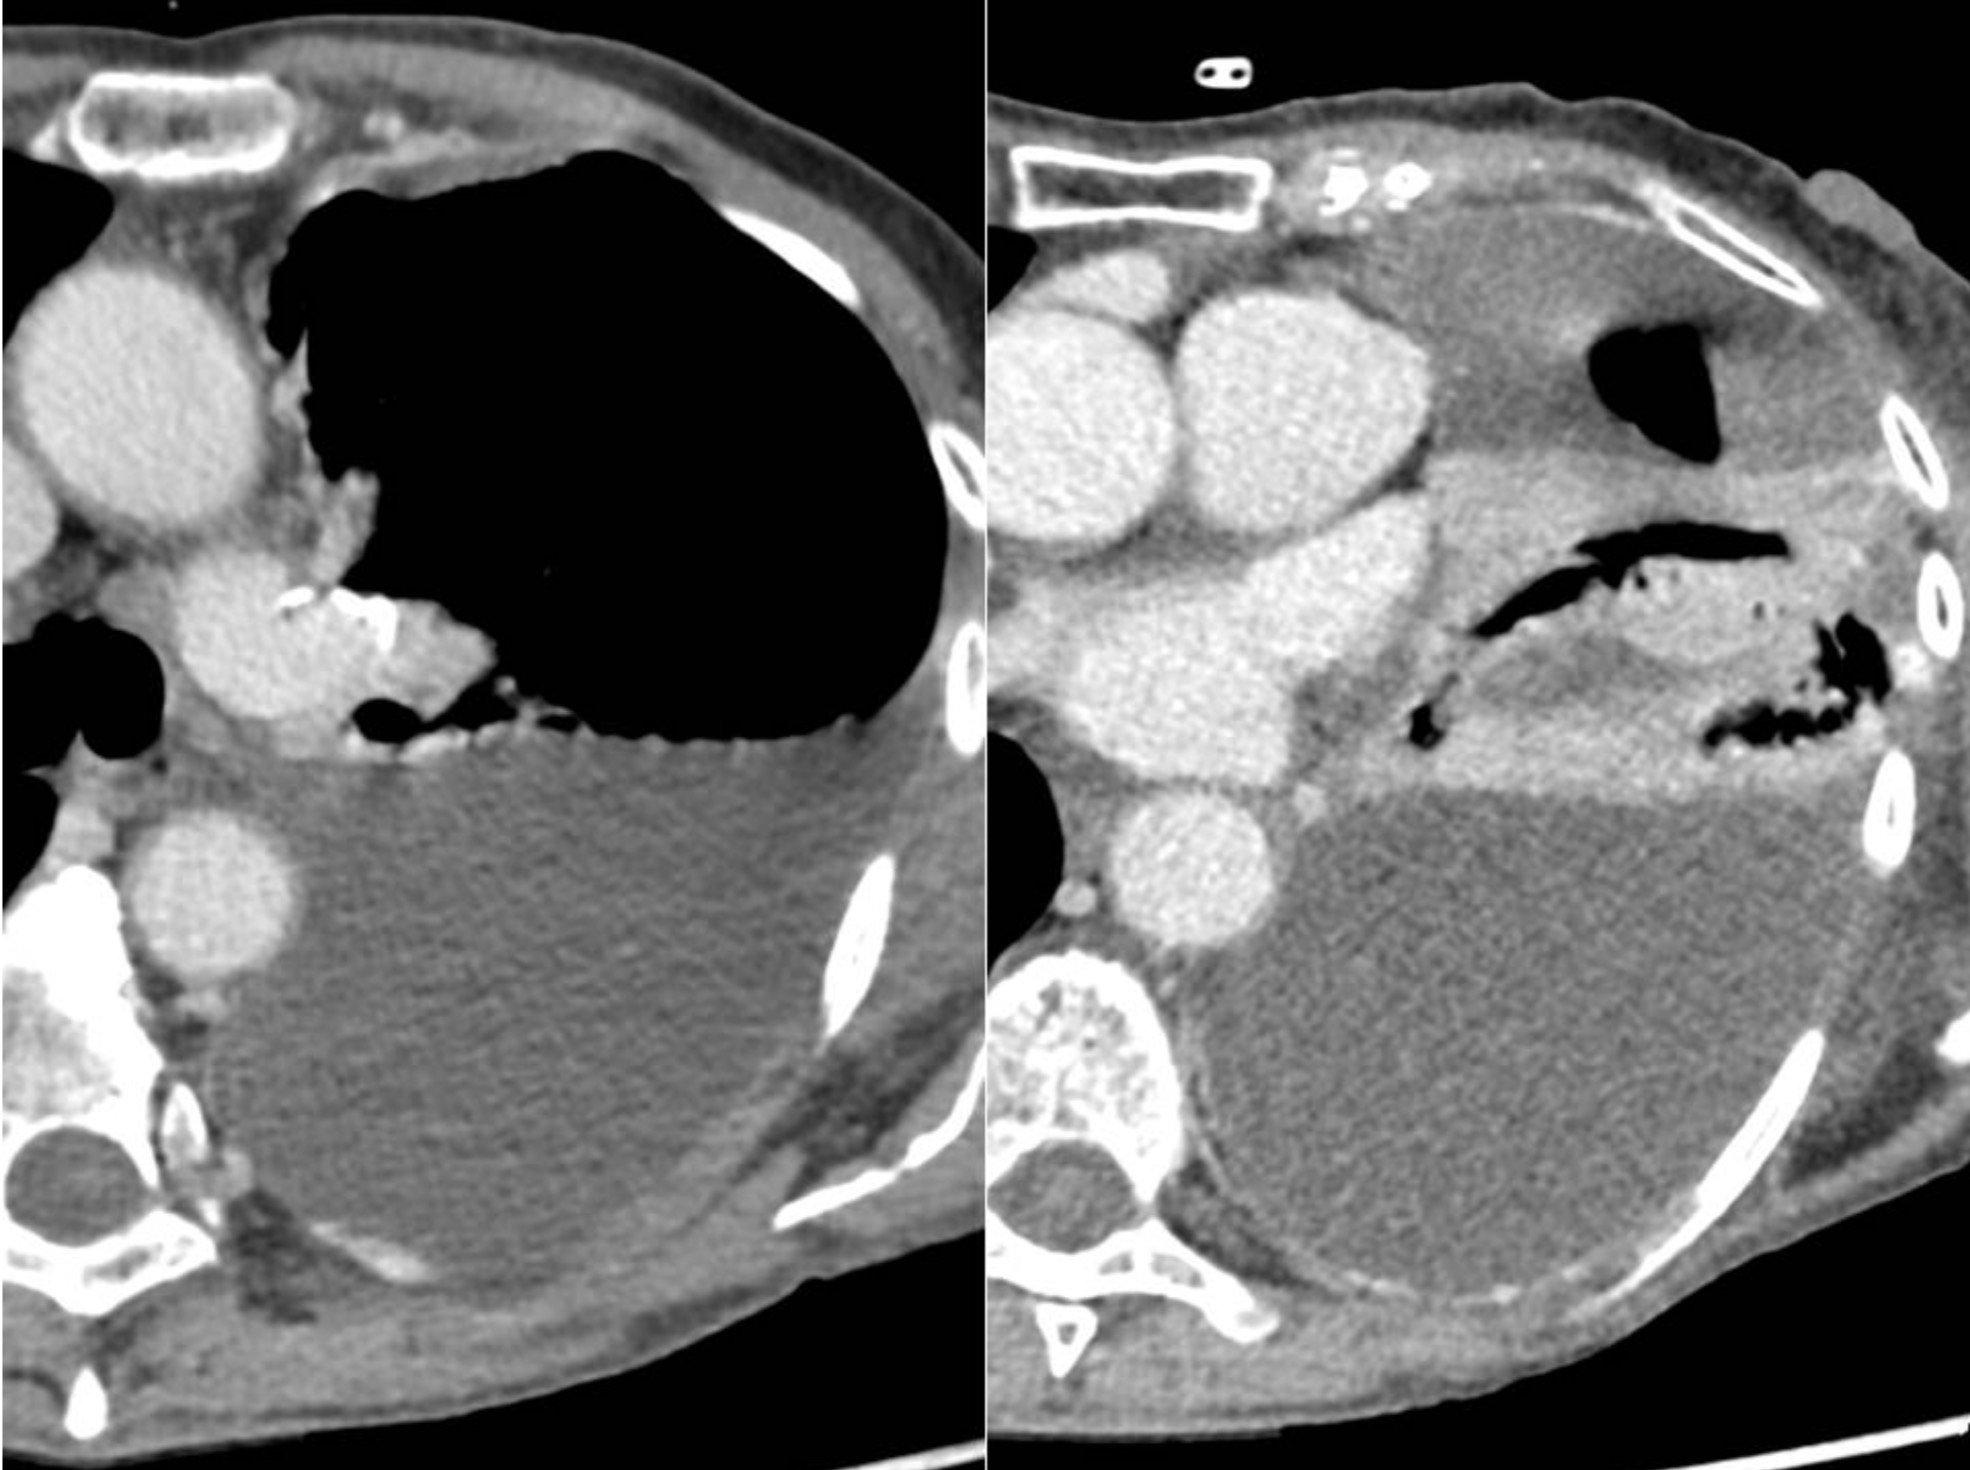

TC de tórax con contraste IV

HALLAZGOS RADIOLÓGICOS